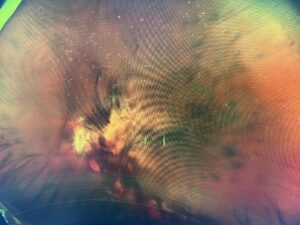

外来を終えてから、ORTのリーダーに検査してもらいました。当院の検査メニューに沿って、先ずは散瞳なしで、広角眼底撮影を6方向とOCTでの硝子体描出モードで確認しました。

リーダーは撮り終えたあと、大丈夫そうですが、確認してみてくださいと言ってデータを送ってくれました。データを確認し、今のところ問題ないと診断、それにしても、リーダーは綺麗に撮るなと感心しながら安心して夜帰ろうとしたところ、外が暗くなっていたので、初めて光視症が出ているのに気がつきました。